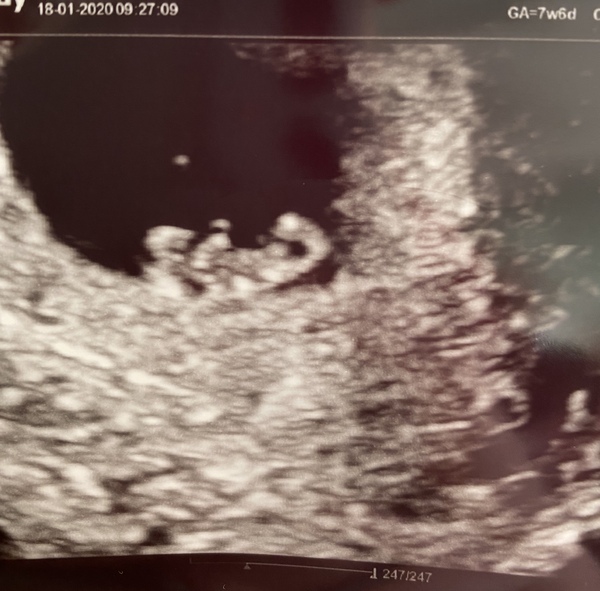

reginafalange2020 · 27/01/2020 18:50

7 weeks 4 days internal scan